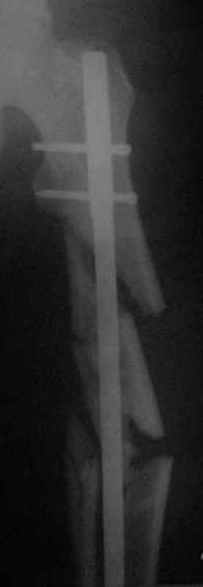

Здравствуйте коллеги!10.07.2006 года поступил молодой человек 26 лет с Диагнозом:

Открытый (2 В Каплан) многооскольчатый перелом левого бедра. Перелом межмыщелкового возвышения большеберцовой кости без смещения слева. Открытый (1 А Каплан) перелом с/3 -н/3 костей правой голени, перелом пяточной кости справа.На седьмые сутки выполнены операции:1. ЗИМО (статически, Chm-CHARFIX) левого бедра. 2. Остеосинтез стержневым аппаратом костей правой голени и пяточной кости. См. r-gr.На сегодня аппарат демонтирован, больной ходит с ограниченной нагрузкой.Смущает стояние отломков в верхней трети бедра (как то не задумались при планировании операции о реконструктивном или гамме штифте ) хватит ли этих двух винтов для стабильности?С Уважением Владимир Бахарев.

Длина проксимального отломка тут достаточна для использования любого диафизарного гвоздя, так что в этом отношении как раз все в порядке. Запас прочности, однако, тут для ранней полной нагрузки недостаточен, и даже с реконструкционным было бы немногим больше - дистальные винты те же 4,5 мм, а они у гвоздей ChM довольно хлипкие. Так что с нагрузкой тут лучше не спешить до уверенных признаков пластики на снимках.

Видна заметная наружная ротация центрального отломка. Если это не случайно сделали снимок, не выведя колено в нейтральное положение, то это типичное смещение, если делать синтез на тракционном столе с тазовой подставкой и промежностным упором. Стоило бы сделать снимок обоих тазобедренных суставов при одинаково уложенных коленных. Для этой же цели можно сделать и снимок в сгибании 90 градусов коленых и тазобедренных суставов, будет прямо видно

антеверсию шеек. Спасибо за презентацию непростого пациента.